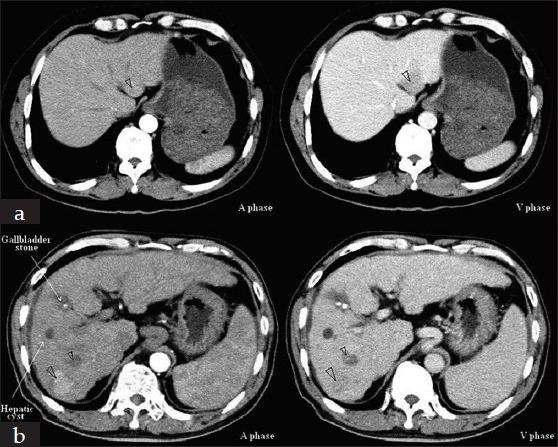

This report describes a 66-year-old male who had a long history of hepatitis B virus (HBV) infection. He was found hepatocellular carcinoma (HCC) 5 months after lamivudine resistance mutation and then received a successful hepatectomy. Three years later, hepatitis B envelope antigen seroconversion was achieved and nucleoside analogs were discontinued. After the withdrawn of antiviral treatment, HBV reactivated and acute-on-chronic liver failure (ACLF) occurred. Anti-HBV treatment improved the patient clinical condition. Three months after the remission of ACLF, the patient was diagnosed as HCC recurrence and received another hepatectomy. This case illustrates indefinite duration antiviral therapy and tight viral control should be performed in patients with HBV-related HCC.

本报告描述了一名66岁男性,他有长期乙型肝炎病毒(HBV)感染史。在拉米夫定耐药突变5个月后被发现患有肝细胞癌(HCC),随后接受了成功的肝切除术。三年后,实现了乙肝e抗原血清学转换,核苷类似物停药。抗病毒治疗停药后,HBV重新激活,发生了慢加急性肝衰竭(ACLF)。抗HBV治疗改善了患者的临床状况。ACLF缓解三个月后,患者被诊断为HCC复发并接受了再次肝切除术。该病例表明,对于HBV相关HCC患者应进行无限期抗病毒治疗并严格控制病毒。